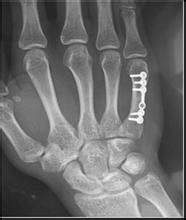

3.微型鋼板、螺絲釘內固定直的鋼板適用於掌骨及近節指骨幹損形或短斜面骨折;“L”型或“T”型鋼板適用於關節內骨折;手指近側指間關節或拇指指間關節的髁骨折可用一個螺絲釘內固定;掌、指骨幹大斜面或螺鏇骨折,其骨折線長度為骨幹直徑2倍以上者用兩枚螺絲釘內固定。近節指骨的直徑與螺絲釘的直徑比例以25:1為合適。。對於皮膚有捻挫傷或多發骨折,由於軟組織損傷較嚴重,手術暴露的範圍太廣,容易增加感染的機會。

多由直接暴力如打擊或擠壓傷所造成,可以為單一或多個掌骨骨折。骨折類型以橫斷和粉碎者多見,因扭轉和間接暴力亦可發生斜形或螺鏇形骨折。由於屈指肌和骨間肌、蚓狀肌的牽拉,骨折向背例成角。對於掌骨幹穩定性骨折,通過手法復位後,可用小夾板外固定。在臂叢神經阻滯麻醉下,在碗關節輕度背伸下,牽拉患指,糾正重疊畸形,術者在掌骨骨間隙擠壓並糾正其側方移位,最後屈曲掌指關節,用拇指置於手掌推擠掌骨頭及骨折遠端向背側,其他四指置於手背骨折的近側段,以糾正向背成角畸形,如果穩定,可以使用支具固定,一般固定4—6周,但要每周複查X線片,如有移位需手術切開。對閉合性不穩定性掌骨幹骨折、多發掌骨幹骨折或手部腫脹嚴重的穩定性骨折以及開放性骨折,為了使其能早期進行功能練習,防止關節僵硬,以切開復位、內固定為宜。開放性骨折的內固定主要選用克氏針內固定,從掌骨頭打人,為了加強其穩定性還加用1根克氏針橫行固定相鄰掌骨的遠側部分,即可防止鏇轉畸形,並維持遠側掌橫弓,對於第二、三學骨,因腕掌關節基本上無活動,因此縱行克氏針可固定至其近端之腕骨。若第二至五掌骨均有骨折,其橫行固定之克氏針要用兩根,才能維持掌橫弓。閉合性拿骨幹骨折切開復位時,單個掌骨骨折用縱s形切口,而多個掌骨骨折時用橫S形切口或兩個縱形切口。切開皮膚後注意保留兩根手背淺靜脈,以免術後患手腫脹。內固定器材可選用微型鋼板、克氏針或鋼絲等。